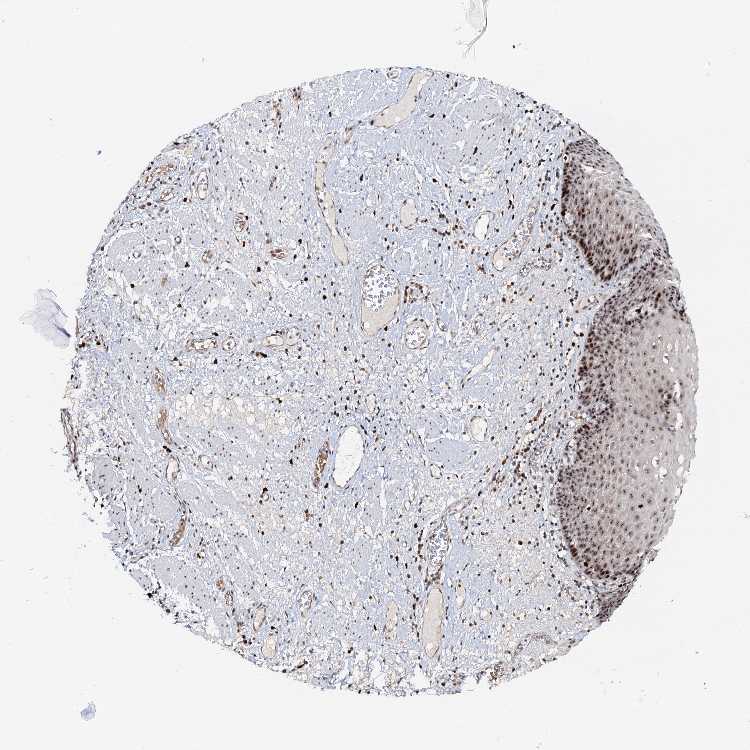

ESOPHAGUS - Antibody stainingi

Antibody staining in the annotated cell types in the current human tissue is reported as not detected, low, medium, or high, based on conventional immunohistochemistry profiling in selected tissues. This score is based on the combination of the staining intensity and fraction of stained cells.

Each image is clickable and will lead to virtual microscopy that enables deeper exploration of all samples and also displays staining intensity scores, fraction scores and subcellular localization as well as patient and tissue information for each sample.

Antibody HPA039785

Squamous epithelial cells Medium